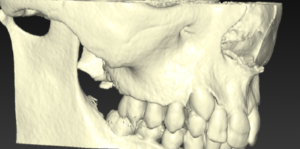

Le dégagement chirurgical de dents incluses​

On constate parfois que certaines dents (canines essentiellement ou incisives) peuvent rester emprisonnées dans l’os de la mâchoire.

On appelle ce phénomène des dents incluses ou en rétention. Il faut donc les dégager chirurgicalement pour coller une attache et pour donner un accès à l’orthodontiste de façon à ramener la dent à sa place sur l’arcade.